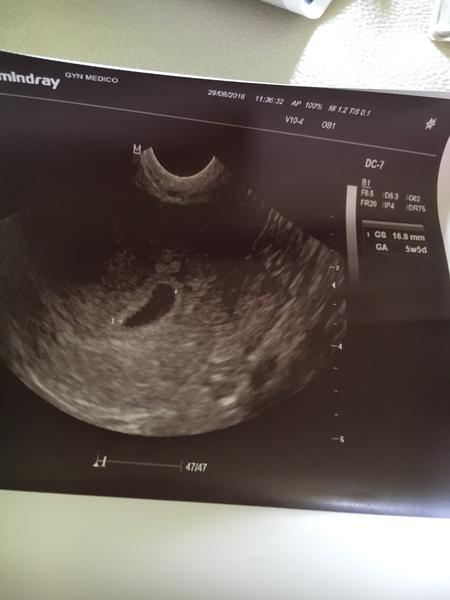

@simi1510 a ty víš, kdy jsi měla ovulaci? 7+2 už by měl být gestační váček, i srdíčko, ale jen za předpokladu, že ovulace skutečně byla 14. den cyklu. Já měla ovulaci vždy až 16-18. tý den cyklu, takže u mě v tu dobu srdíčko ještě nebylo a doktor si mě vždycky zval až v 8tt nejdřív.

@simi1510 jako promiň co teď řeknu, ale ta doktorka je normální kr.va, protože progres samozřejmě je. Dneska krásná bublinka a už vidím i náznak plodu. Pokud byla ovulace až takhle pozdě, tak všechno sedí. Samozřejmě můžeš potratit, to je něco co se stane když to nečekáš a těhotenství od začátku šlape a vyvíjí se a stejně v 9tt konec. Ale teď bych se nestresovala, i když mě se to mluví, chápu jak se cítíš. Mě nervovali vždycky všichni taky a nikdo nechtěl chápat, že mám ovulaci až skoro o týden později. HCG ti neřekne nic, musela bys chodit každé dva dny a i tak to nepoznáš. Vydržela bych týden do dalšího ultrazvuku a tam se už uvidí. držím palce (hug) není tu objímající smailík 🙂

@denikzaslouzilemamy debilni ruska... Ze misto 7+2 dle ms to odpovídá 5.tydnu